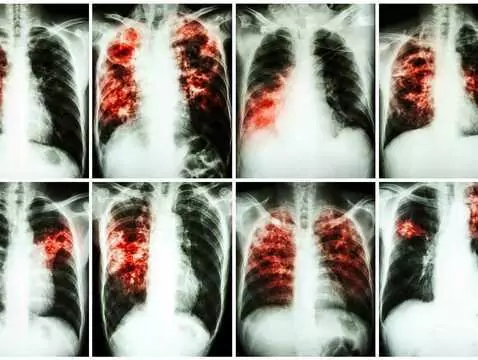

Rak płuca to jedno z największych wyzwań współczesnej onkologii w Polsce i na świecie – pozostaje najczęstszą przyczyną zgonów z powodu nowotworów złośliwych, a liczba zachorowań rośnie z roku na...

Kolejna lista refundacyjna przyniosła bardzo dobre informacje dla chorych na raka płuca. Tym razem od 1 marca rozszerzeniu uległ program leczenia drobnokomórkowego raka płuca, który w nowej odsłonie...

Leczenie raka płuca w Polsce przeżywa prawdziwy renesans. Dekadę temu diagnoza nowotworu płuca oznaczała dla większości pacjentów wyrok. Dzięki dostępności do nowoczesnego leczenia, coraz częściej...